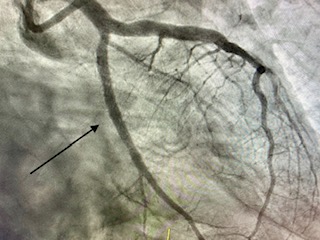

Angioplastia con stent

La angioplastia coronaria transluminal percutánea con implantación de stent ha sido capaz, en las salas de RX de los laboratorios de Hemodinámica y Cardiología Intervencionista, de combatir eficazmente a la enfermedad que más mortalidad causa en las sociedades modernas: la enfermedad coronaria.

Angioplastia con stent en un infarto (arteria cerrada 100%)